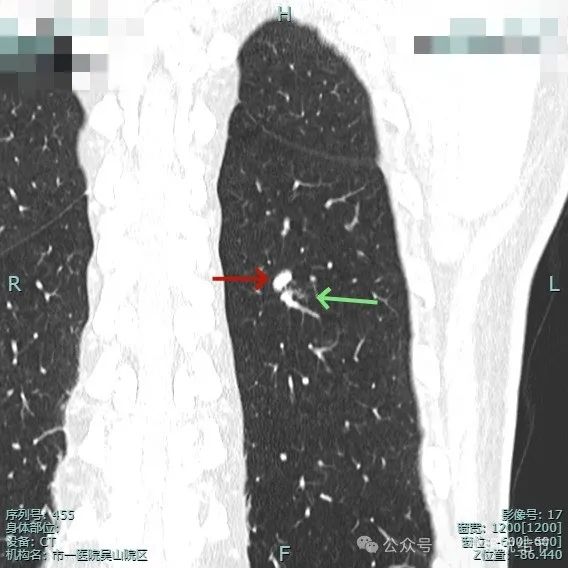

边缘毛糙,细毛刺或锯齿状明显。

整体膨胀性较明显,有少许磨玻璃成分,周围肺野较清晰,血管与之关系密切。

细小毛刺可见,少许磨玻璃成分,整体轮廓较清。